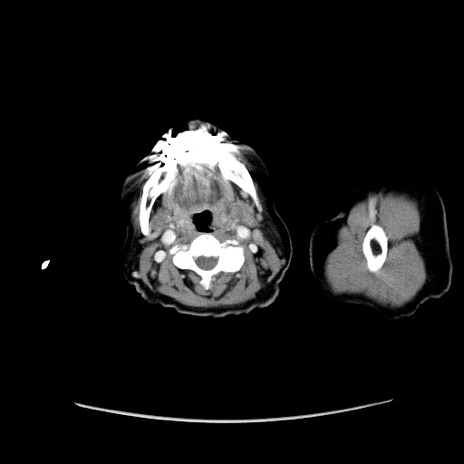

症例19(横断像)

【症例】80歳代女性

【主訴】下腹部痛

【現病歴】約8時間前より下腹部痛の出現あり、救急外来受診。

【既往歴】両側付属器切除

【身体所見】意識清明、下腹部正中に手術痕あり、その部位に一致して圧痛と反跳痛あり。腸蠕動音は亢進。

【データ】WBC 9300、CRP 0.15